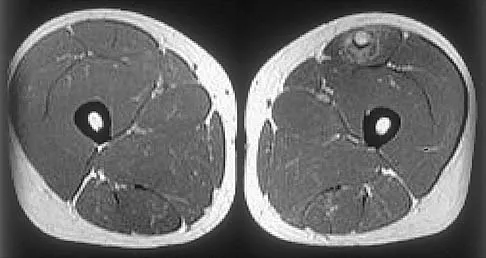

Figures 34a through 34c show an axial proton density (spin echo long TR, short TE) image, a sagittal inversion recovery (STIR) image, and a sagittal T1-weighted (short TR, short TE) image of the left thigh. What is the most likely diagnosis?

Explanation

The images reveal a region of increased signal within the rectus femoris muscle with mild, ill-defined surrounding edema. The presence of high intensity signal on the T1-weighted image favors acute blood, in this case associated with a rectus femoris muscle tear or fatty tissue. However, because of fat suppression, a fatty lesion or lipoma would be dark on STIR, rather than bright as in this image. Most foreign bodies are low intensity signal and if small, are difficult to evaluate with MRI. The lack of adjacent subcutaneous soft-tissue edema or surrounding fluid makes pyomyositis an unlikely diagnosis.